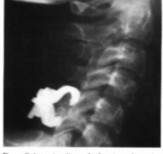

Các tác giả thấy rõ rằng sự lỏng vít xảy ra ở 2 nơi, một là chỗ tiếp xúc vít-nẹp, và hai là chỗ vít-xương. Leventhal [81] dùng nẹp khóa Morcher (H 1.31B) khắc phục được 2 nhược điểm trên. Nẹp khóa vào vít, vít có lỗ để xương mọc vào, nhờ vậy mà tránh được sự lỏng vít, tuột ghép. Nẹp khóa khá đắt tiền.

Hình 1.31: A: Nẹp vít hai vỏ xương; B: Nẹp khóa Morcher. Nguồn : Leventhal (1998), Campell’s operative orthopeadics [81].